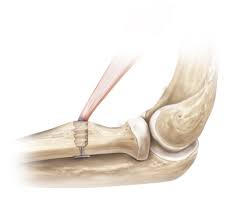

Biceps Tenodesis Protocol

Distal biceps tendon repair protocol